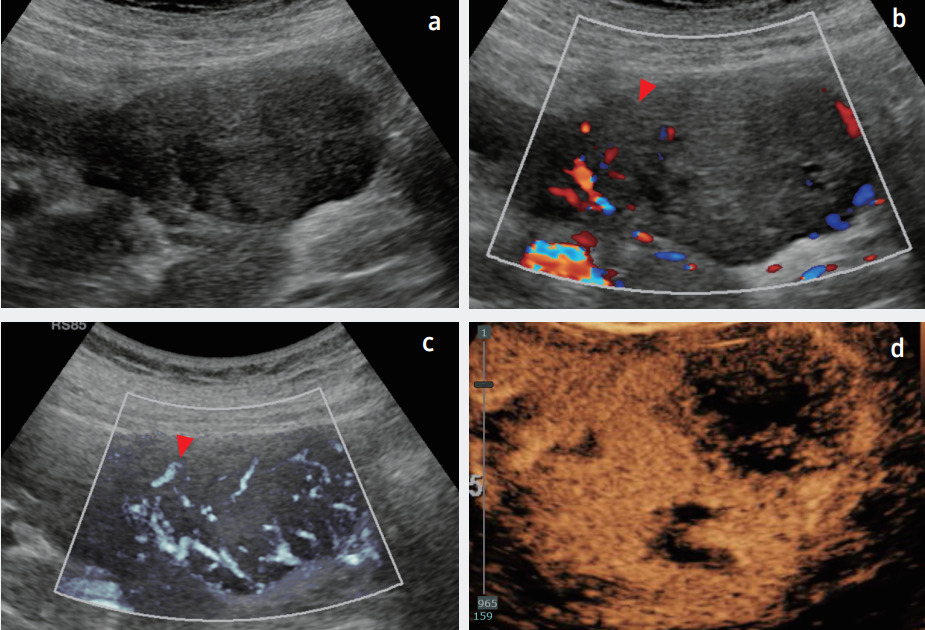

Высокая чувствительность к низкоскоростным кровотокам повышает точность диагностики. На снимке пример визуализации карциномы почки в В-режиме, цветовом допплере, MV-Flow и CEUS.